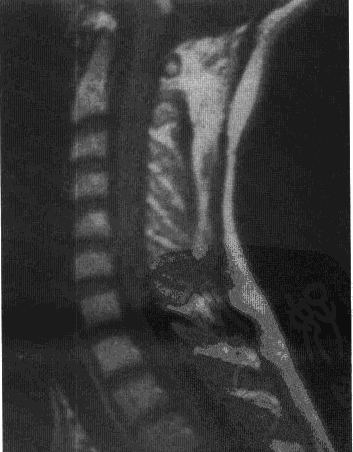

脊髓血管母细胞瘤大多位于脊髓背侧,近背根人脊髓处,胸段较常见,颈段次之。髓外硬膜下血管母细胞瘤常常附着于脊神经后根或终丝。髓内血管母细胞瘤约50%伴脊髓空洞,类似于小脑血管母细胞瘤的囊肿,MRIT2加杈像适于鉴别空洞和水肿由于脊髓血管母细胞瘤大多位于背侧,故广泛切除椎板中间部分即能达到允分暴露腹侧肿瘤大多采用后外侧入路,切除椎板、关节面和椎弓根,轻柔拨开脊髓以显露病变,亦有采用前方入路者。若增粗的软膜血管不能帮助判断肿瘤位置,术中超点可以帮助肿瘤定位。与小脑血管母细胞瘤一样,脊髓血管母细胞瘤被一层软膜包被而存在明显边界,使其易与脊髓分离,完全切断滋养血管后,瘤结节可以完整切除,同样,脊髓血管母细胞瘤不宜取活检或分块切除,空洞壁应予以保留。